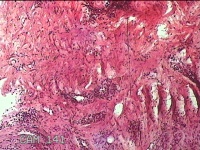

性别

女

年龄

47岁

临床诊断

纤维瘤

一般病史

面部新生物一月余。

标本名称

面部赘生物

大体所见

灰白粉红色肿物0.8x0.7x0.3cm一个,表面糜烂。